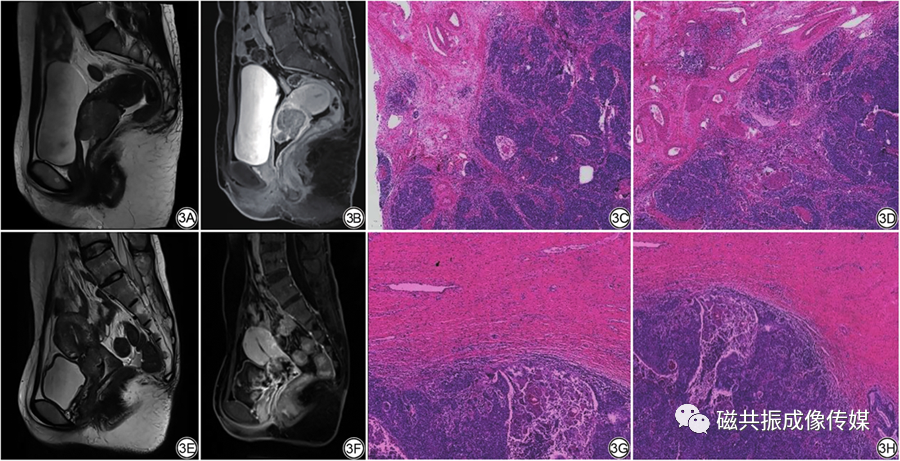

宫颈癌骨转移

宫颈癌骨转移,骨转移癌

肿瘤介入—宫颈癌病例分享一

宫颈癌转移到骶骨严重吗

骨转移

骨转移图片